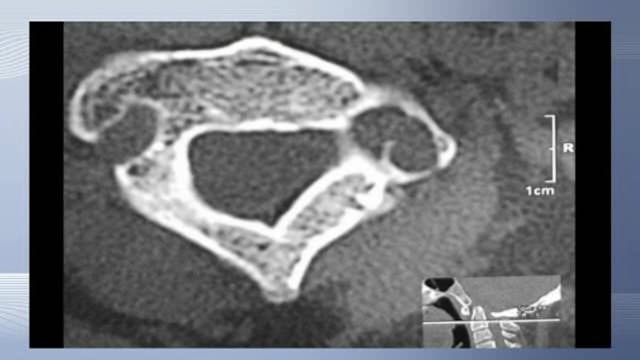

Direct screw fixation of spondylolysis without fusion

Deformities and Malformations Adult • 15m